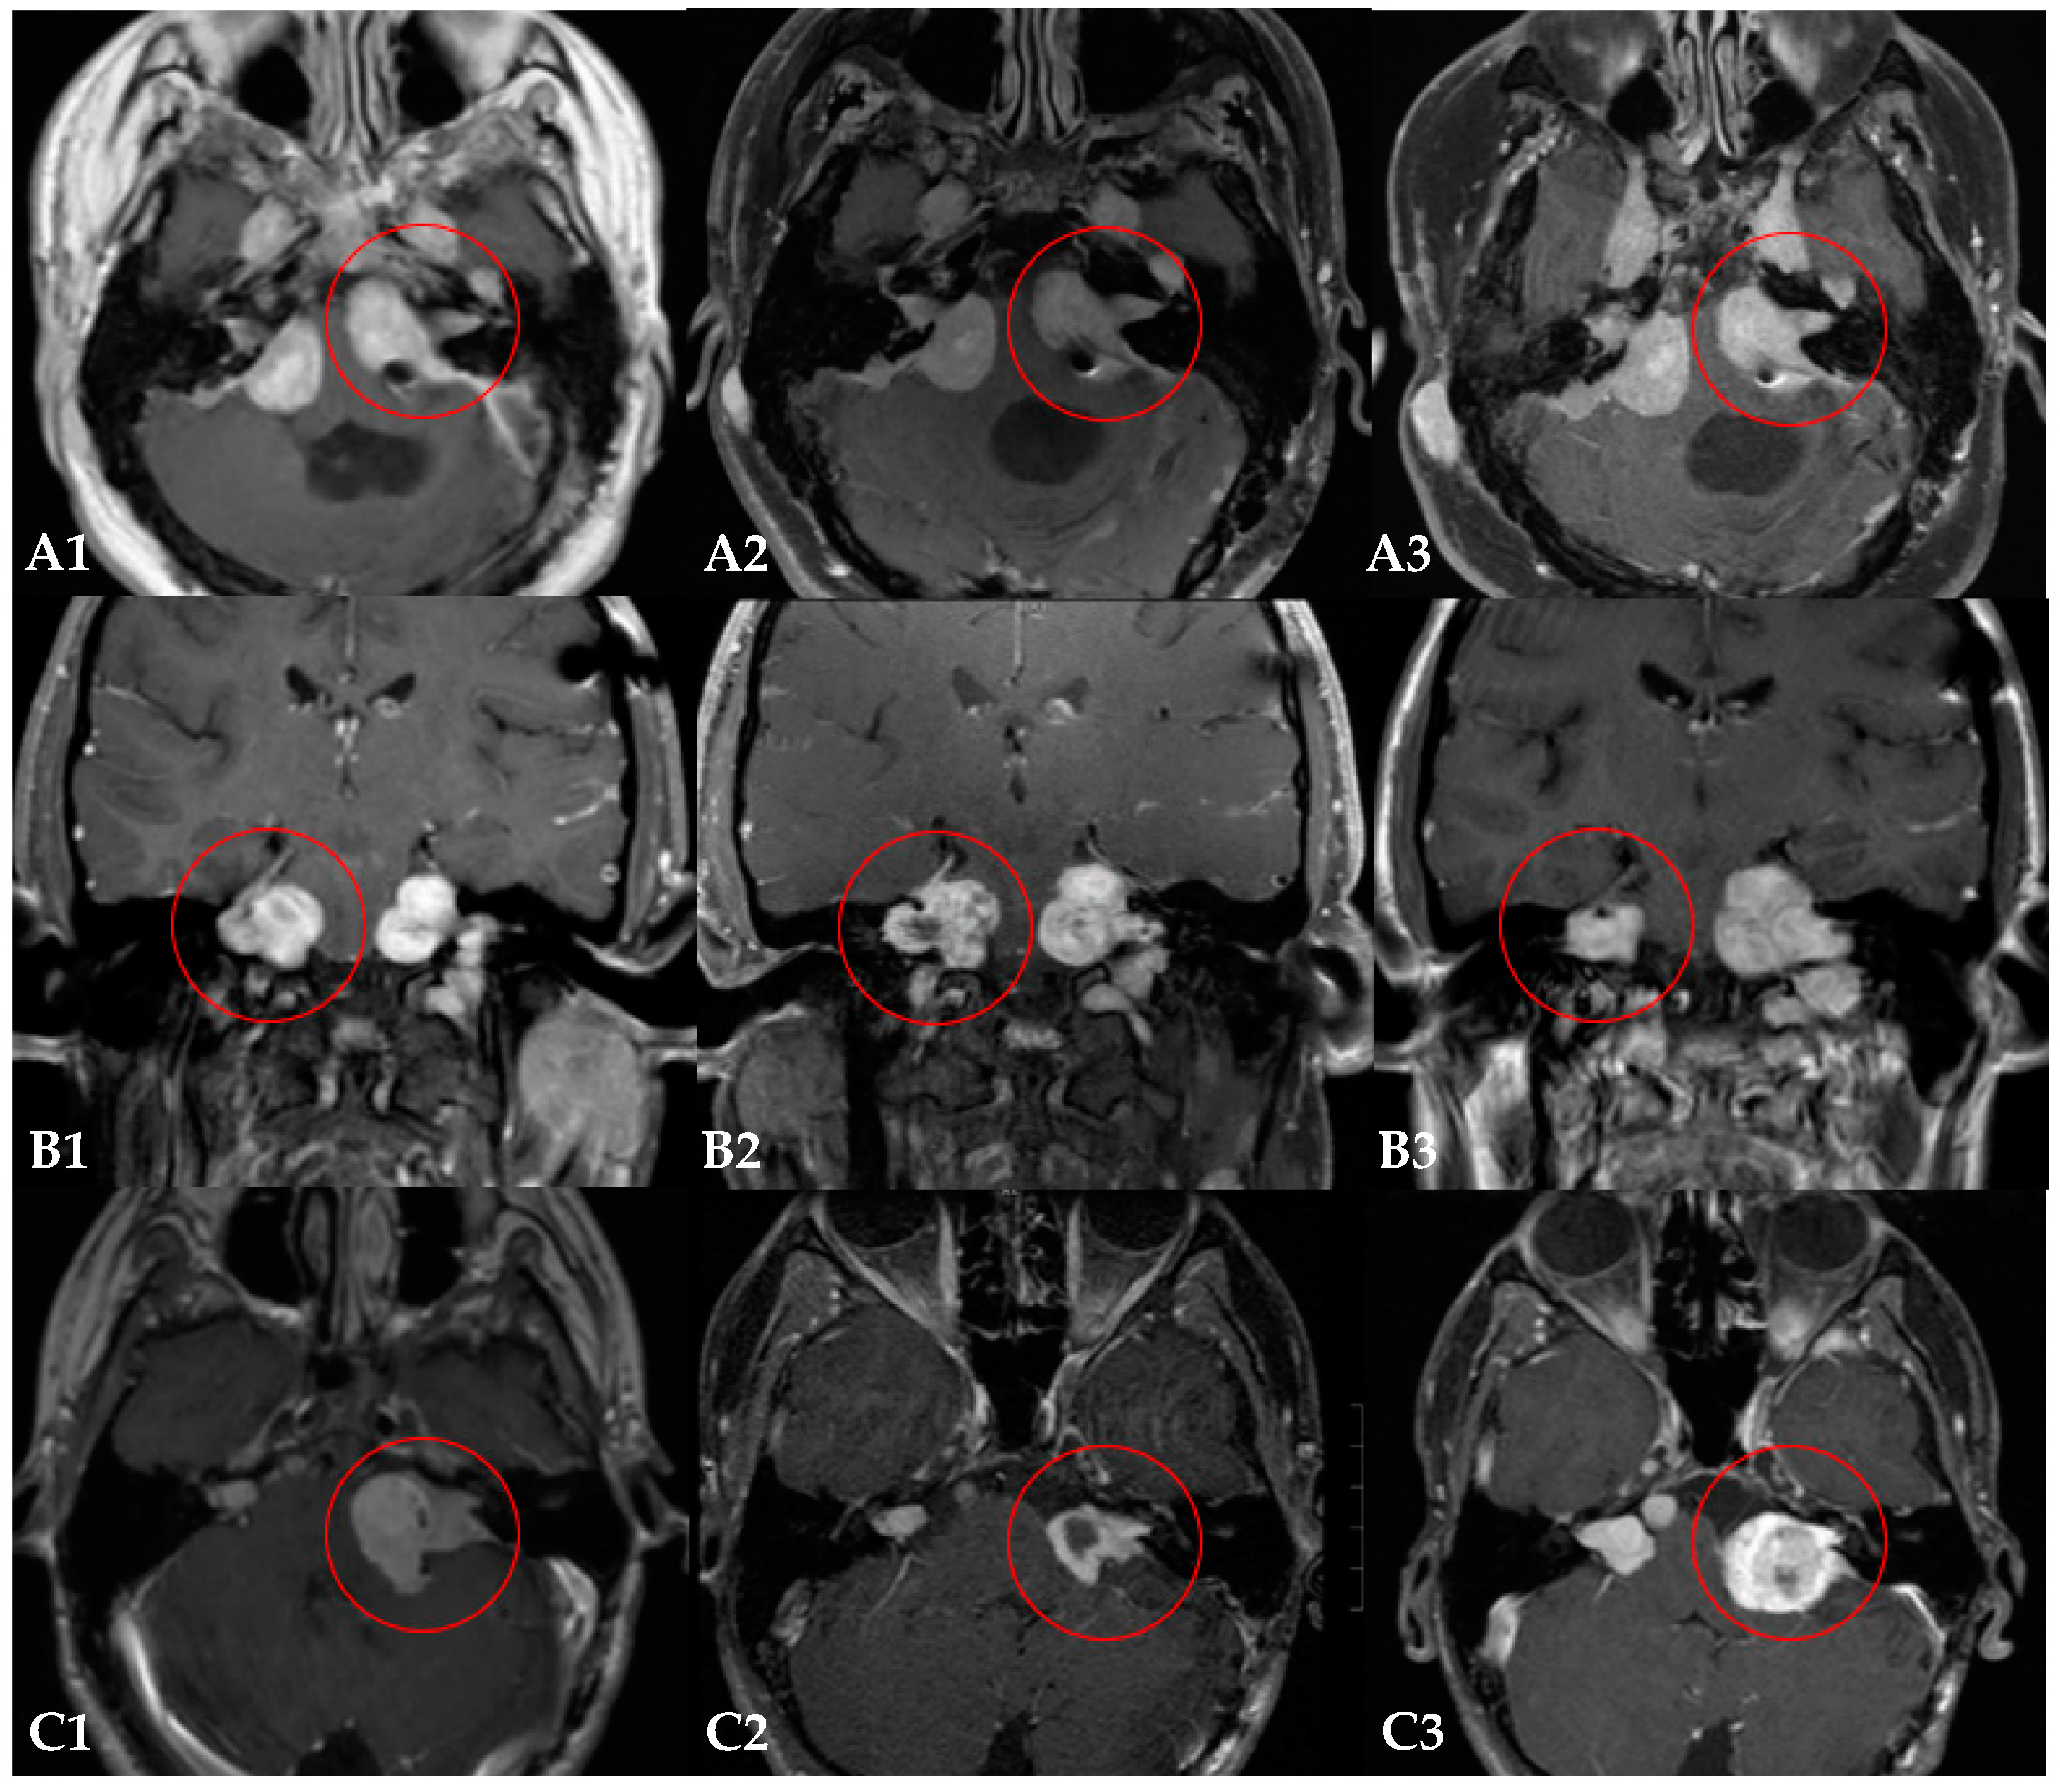

The median tumor volume was 4.2 cm3 (IQR 0.9–9.3) prior to PRT. The median radiologic follow-up after PRT was 71 months (IQR 62–85). Six out eight patients (75%) did not require salvage therapy after PRT for the target VS during the follow-up period (Table 3, Figure 1).

Figure 1.

Three examples of the radiological follow-up of Neurofibromatosis Type 2-related vestibular schwannomas treated with proton radiotherapy (PRT). Each row (A–C) represents MR imaging of one patient over time: the baseline MR image (1), the MR image one year after PRT (2), and the most recent MR image (3). Patient (A): the tumor of interest remained stable during the follow-up of 60 months (A1–A3). Patient (B): the initial tumor shrinkage achieved with PRT and adjuvant bevacizumab therapy (B1), was followed by tumor progression (B2) that required additional treatments with bevacizumab (B3). Patient (C): the initial tumor shrinkage (C1,C2) was followed by significant tumor progression (C3), requiring salvage surgery at 87 months after PRT.

Two patients (25%) required additional treatment for tumor progression of the irradiated lesion. In patient #5, adjuvant bevacizumab therapy was required after the PRT, resulting in the initial tumor shrinkage of the irradiated tumor. Due to hearing loss and rapid tumor progression after stopping the adjuvant bevacizumab, bevacizumab was restarted 12 months after the PRT. Substantial tumor shrinkage (−59%) was observed under this course of bevacizumab three months later. During follow-up, patient #5 received several other courses of bevacizumab to maintain tumor control of the target VS (Figure 1, row B). In patient #6, surgical resection was required at 85 months (7 years) after the PRT, due to tumor progression (Figure 1, row C). Another patient (patient #1) received several courses of systemic therapies (bevacizumab, dasatinib, and brigatinib) after the PRT. However, in this case the irradiated tumor remained stable during follow-up and the systemic therapies were indicated for other lesions. The tumor of interest was therefore deemed free of progression after PRT.